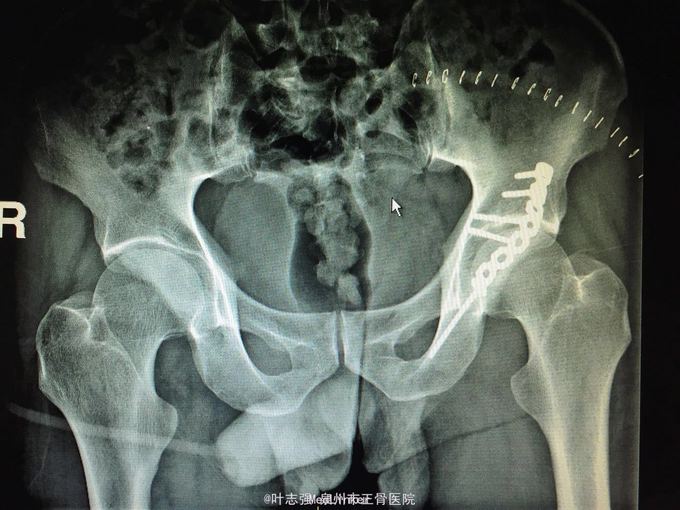

髋臼骨折伴髋关节后脱位ORIF

车祸致左髋部疼痛、活动受限1天。 53岁男性

左髋臼骨折伴髋关节后脱位 行生命支持,股骨髁上骨牵引,